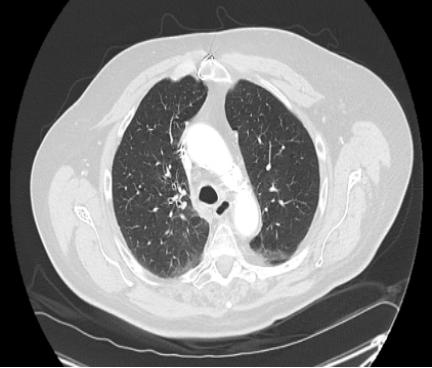

Diagnostic testing. The patient was relatively stable on physical examination during his first visit to the ED, with good bilateral air entry and no wheezing. Laboratory results showed a white blood cell (WBC) count of 4.9 × 10³/µL (4.5 - 11.0 × 10³/µL), hemoglobin of 11.9 g/dL (14 - 18 g/dL), platelet count of 122 × 10³/µL (150 - 350 x 10³/µL), blood urea nitrogen (BUN) of 17 mg/dL (8 20 mg/dL), creatinine (Cr) of 1.13 mg/dL (0.8 - 1.3 mg/dL), and electrolyte levels of sodium (Na) 137 mEq/L (136 - 145 mEq/L ) and potassium (K) 4.3 mEq/L (3.5 - 5.0 mEq/L). Liver function tests (LFTs) were within normal limits. The initial workup included computed tomography angiography (CTA) of the chest, which revealed a right suprahilar mass measuring 3.5 × 2.6 cm (Figure 1), suspicious for malignancy.

Figure 1. Chest CT at the diagnosis showed a right suprahilar mass.